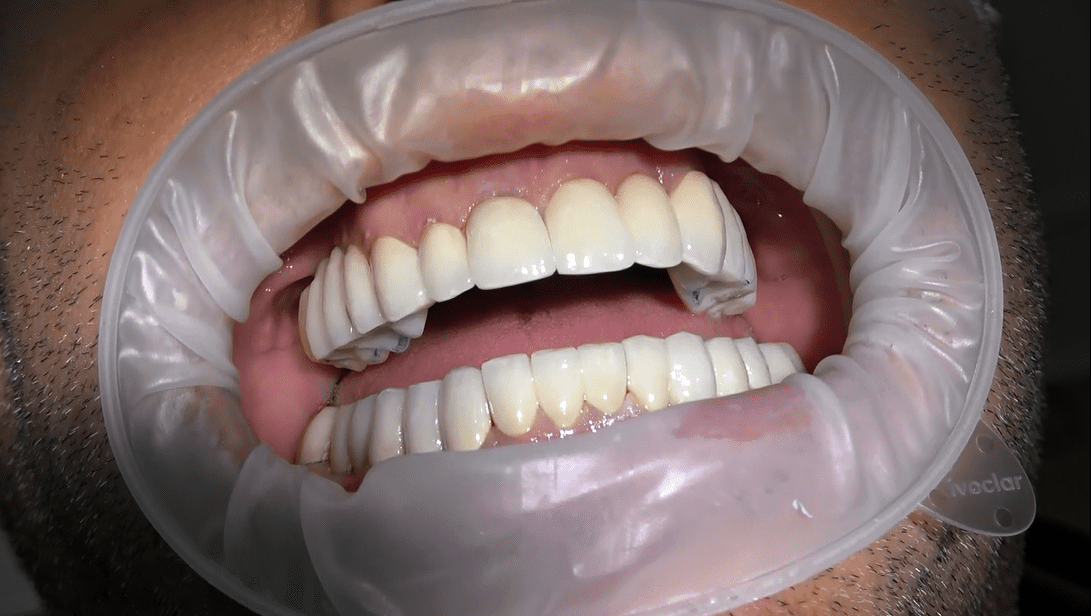

Se stai cercando una soluzione protesica straordinaria che combini estetica naturale e personalizzazione su misura, la nostra Protasi Circolare è ciò che fa per te. Presso il nostro centro specialistico, siamo fieri di offrire protesi dentali uniche, realizzate a mano con cura e dedizione per un sorriso che si distingue per la sua bellezza autentica.

Le nostre protesi circolari senza gengiva sono un capolavoro artigianale, realizzato su misura per ogni paziente. La forma circolare della protesi è studiata per adattarsi armoniosamente alla tua bocca, distribuendo uniformemente la pressione masticatoria e garantendo comfort e stabilità.

• La nostra firma è la protesi circolare senza falsa gengiva. Eliminiamo i confini artificiali per un sorriso che sembra naturale e autentico.

• La nostra galleria fotografica presenta una collezione di sorrisi trasformati grazie alle nostre protesi circolari. Scopri i risultati straordinari ottenuti per i nostri pazienti.

Siamo entusiasti di accompagnarti nella tua ricerca per un sorriso impeccabile. Presso il nostro studio, la protesi circolare diventa un’opera d’arte, creata su misura per te. Contattaci oggi stesso per una consultazione e inizia il tuo viaggio verso un sorriso esteticamente naturale, senza compromessi.